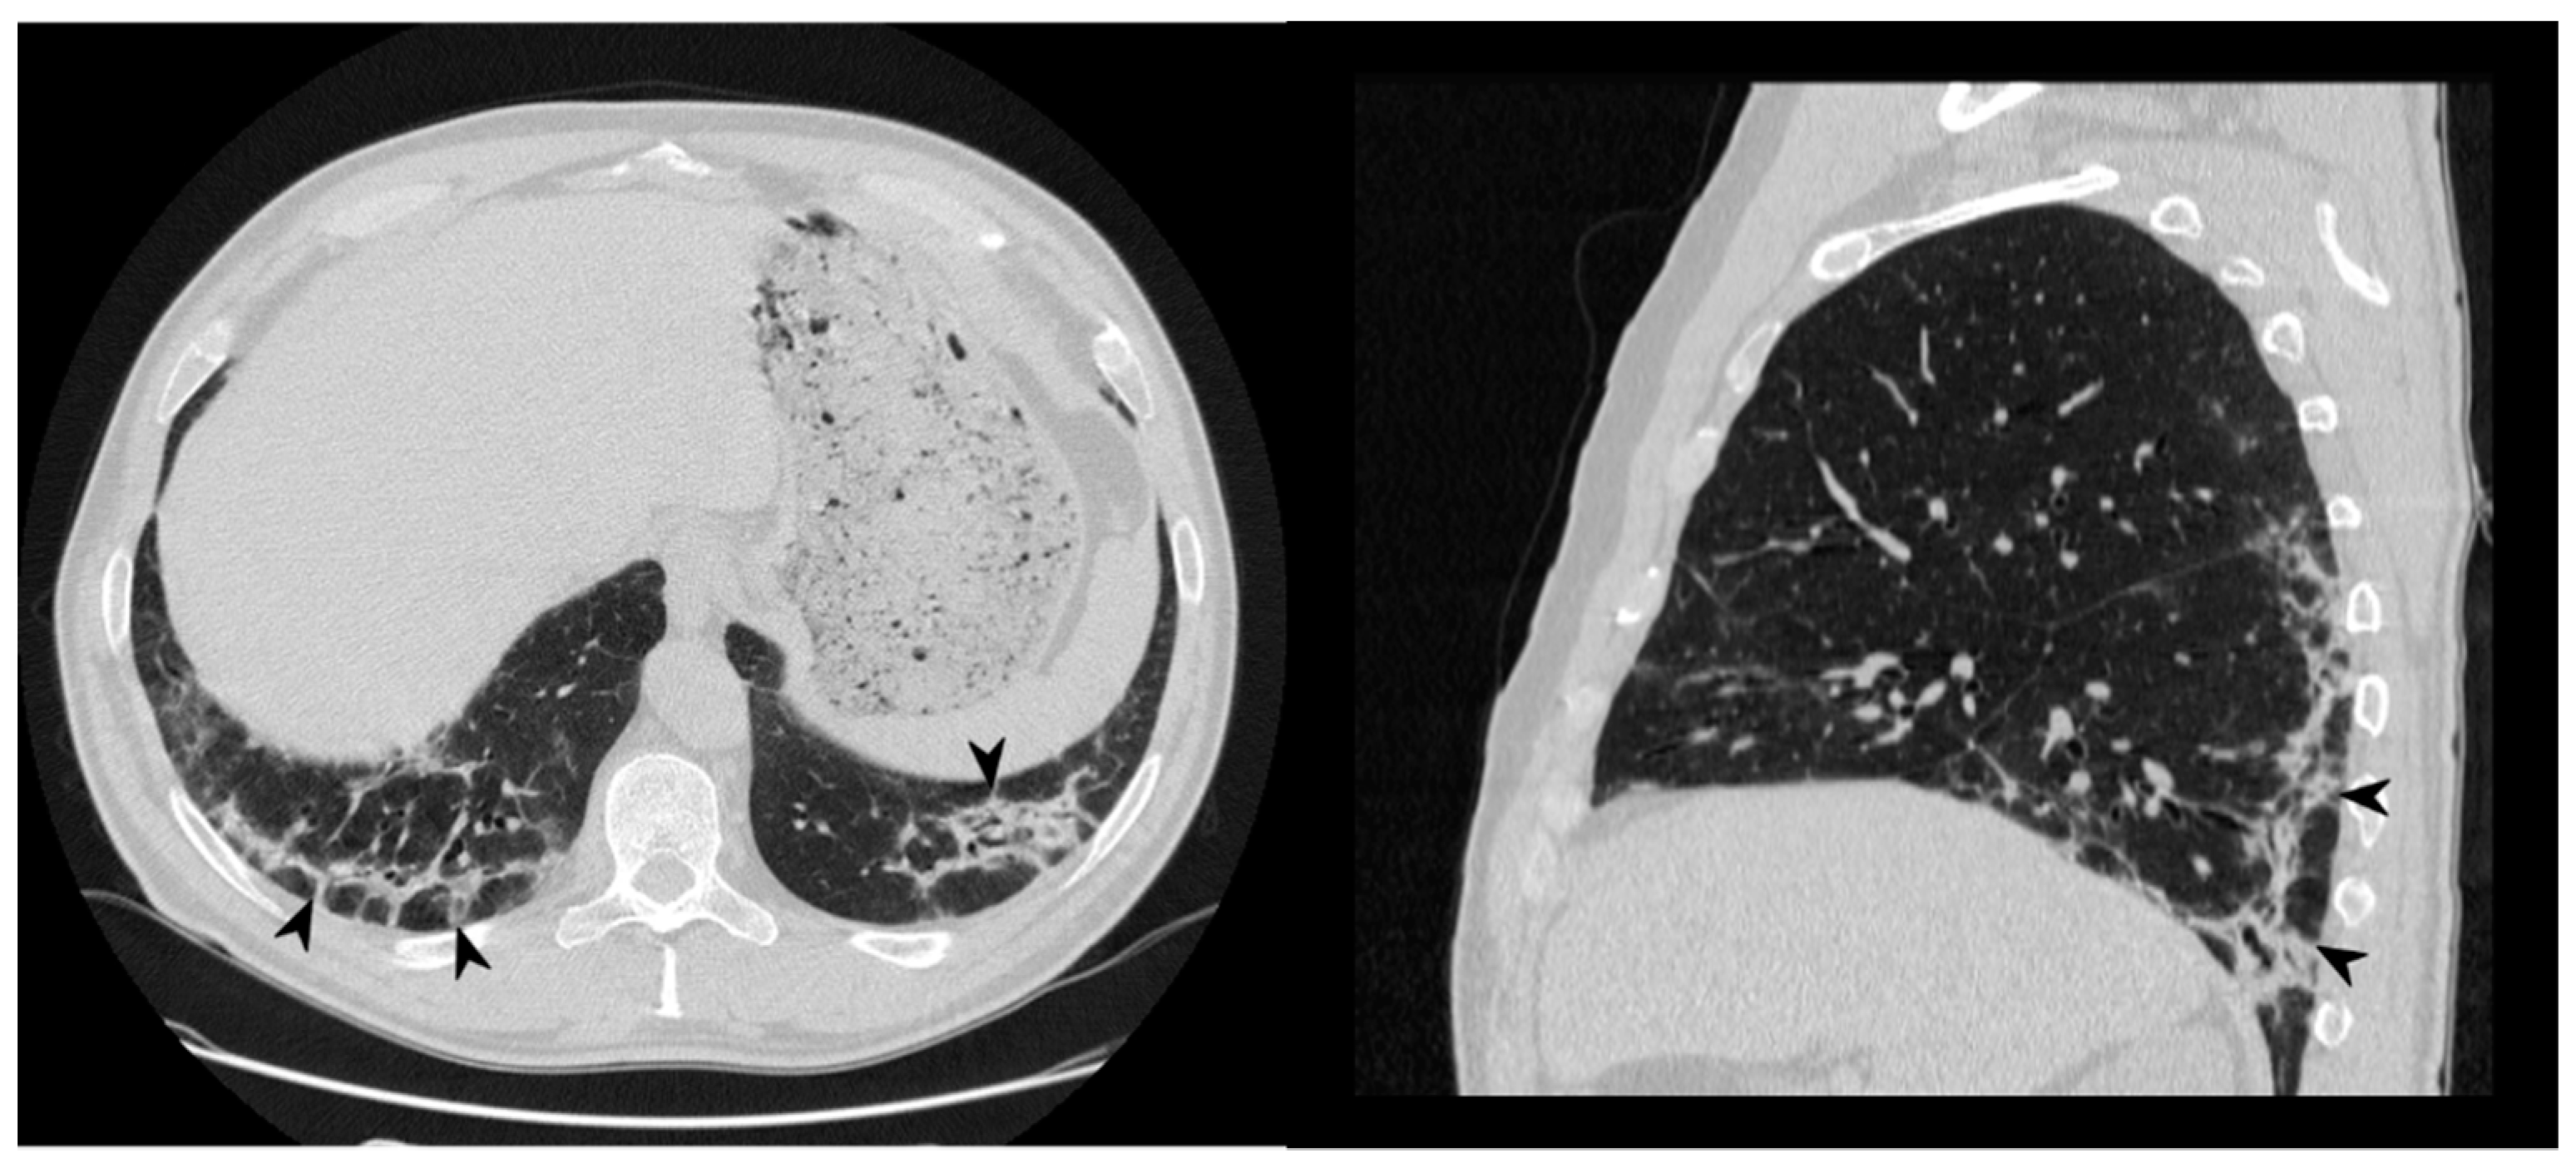

Figure 5. Fibrotic pattern: bilateral sub-pleural reticulations (arrowheads) and architectural distortion, clearly visible in peripheral regions of right lung (a) and left lung (b).

1.3.4. Progressive Fibrosis Pattern

OP can produce sub-pleural basal reticulations and architectural distortion in about a 15% of cases, mimicking the appearance of nonspecific interstitial pneumonia (NSIP); the reticulations coexist with regions of consolidation or appear later (Figure 5) [24]. This presentation seems to be associated with a poor outcome [26]. As reported by OIkonomou et al., this pattern may occasionally result in honeycombing and must be differentiated from usual interstitial pneumonia (UIP) [20]. Pathologically, alveolar epithelial damage is a common condition in both OP and UIP. In OP, the necrosis of alveolar epithelium is followed by the migration of fibroblasts from the interstitial compartment to airways, while, in UIP, fibroblastic foci are restricted to interstitium, and intraluminal fibrosis is less extensive than in OP [20].

Figure 14. On the left: axial view. On the right: sagittal view. Perilobular pattern: the presence of arcade-like bands with blurred borders and thickening of the interlobular septa—resembling a Roman Arch (arrowheads), despite steroid therapy.